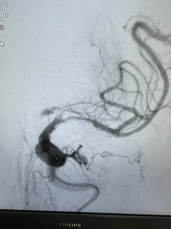

取出的血栓

随即,卒中介入团队快速启动急诊手术流程。11:42,经介入治疗后,梁大爷闭塞血管顺利开通。再次造影显示,患者左侧大脑半球血流恢复。大脑在重新得到新鲜血液灌溉后,因缺血而不完全坏死的脑细胞逐渐恢复生机。